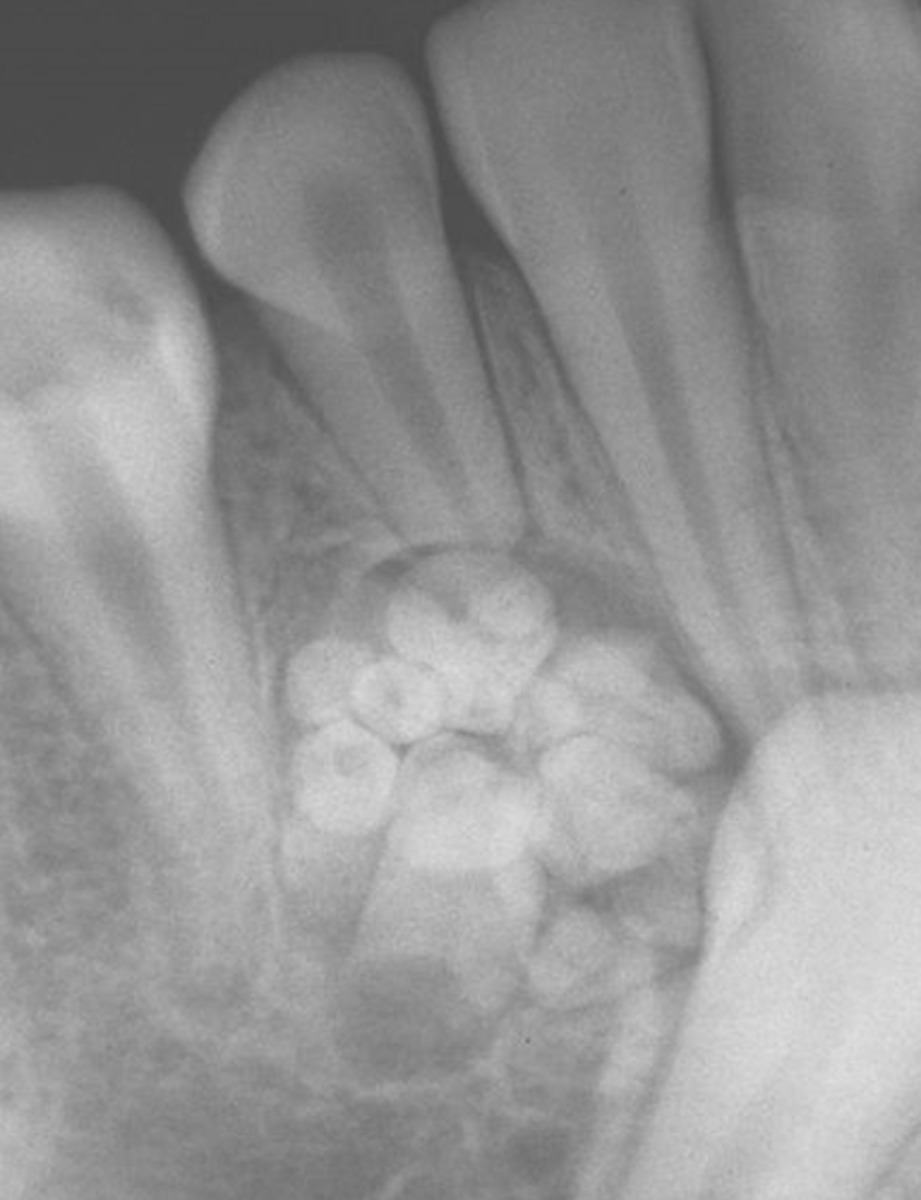

What is the radiographic appearance of compound odontomas?

cluster of miniature teeth (or extra mini tooth)